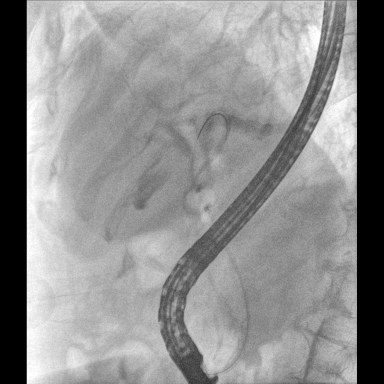

具備血管造影及數(shù)字減影(DSA)、路徑圖(Road-map)、透視、攝影等功能。 廣泛適用于介入科、血管外科、腫瘤科、消化內(nèi)科及骨科等多個臨床科室,典型應(yīng)用包括:TACE(肝腫瘤栓塞與化療灌注術(shù))、心臟起搏器置入術(shù)、四肢動脈造影術(shù)、下肢靜脈濾器置入術(shù)、ERCP(經(jīng)內(nèi)鏡逆行胰膽管造影術(shù))等。

核心DSA軟件可實時生成高清血管影像,結(jié)合路徑圖功能,在手術(shù)中為醫(yī)生提供血管導(dǎo)航。